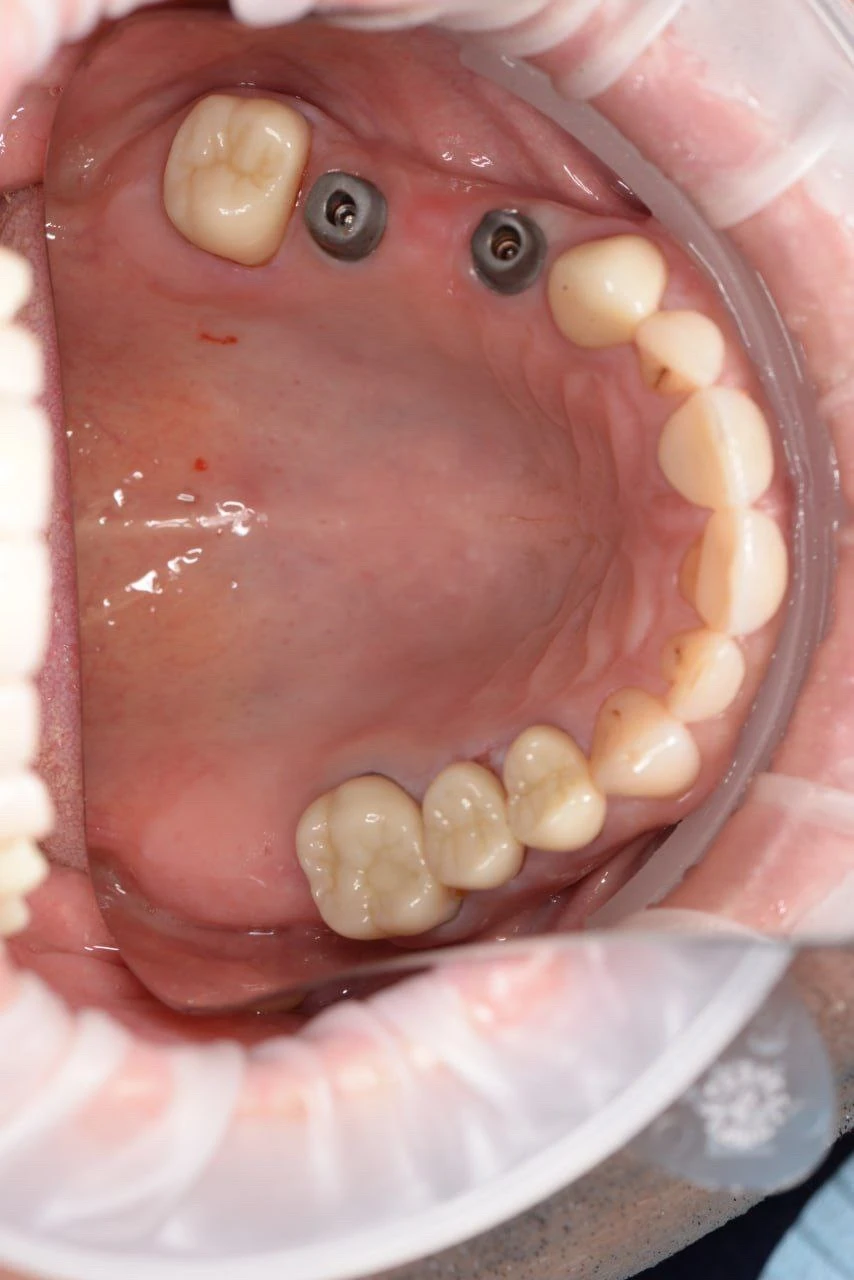

Цирконієва коронка на імпланті 46

Цирконієва коронка 45 та цирконієва коронка 46 на імпланті

Цирконієва коронка 35 та цирконієва коронка 36 на імпланті